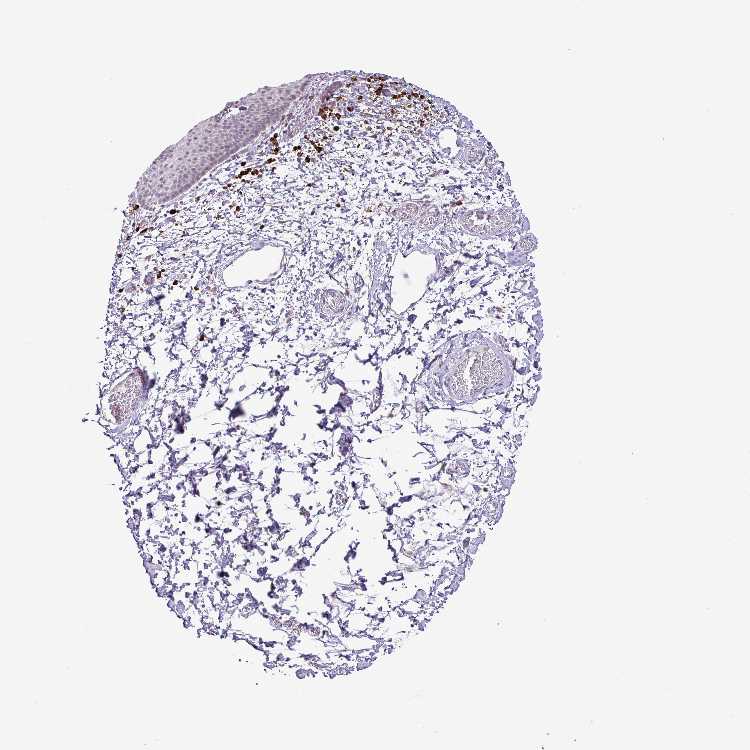

SKIN 2 - Antibody stainingi

Antibody staining in the annotated cell types in the current human tissue is reported as not detected, low, medium, or high, based on conventional immunohistochemistry profiling in selected tissues. This score is based on the combination of the staining intensity and fraction of stained cells.

Each image is clickable and will lead to virtual microscopy that enables deeper exploration of all samples and also displays staining intensity scores, fraction scores and subcellular localization as well as patient and tissue information for each sample.

Antibody HPA052843

Epidermal cells Not detected